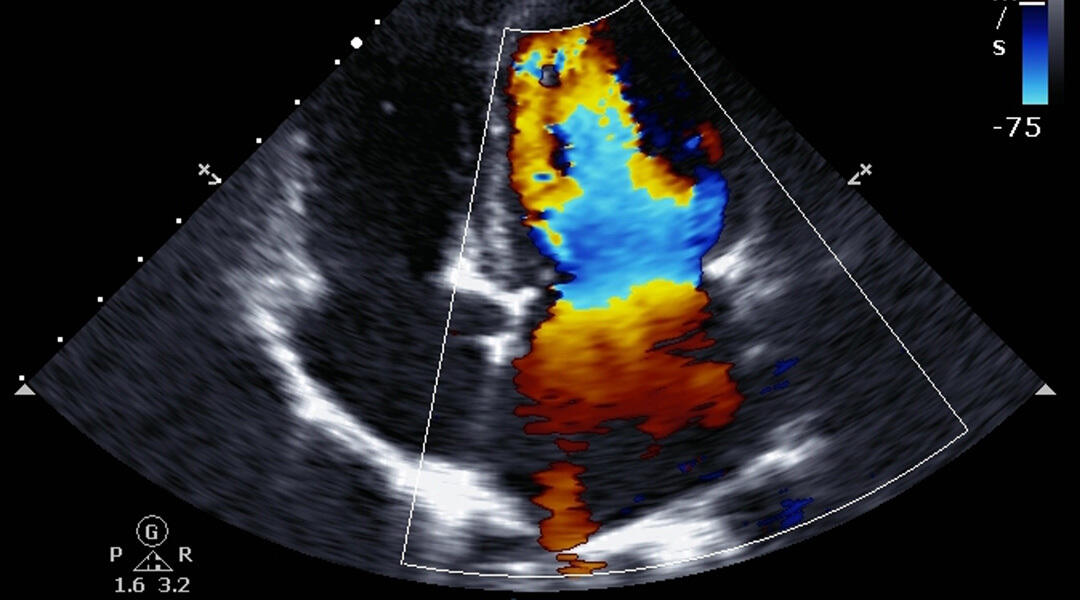

This webinar has been developed in collaboration with the National Heart Foundation of Australia to explore the important role echocardiography plays in the diagnosis and classification of heart failure. It has been designed to enhance GP awareness of the importance of echocardiogram referral and increase confidence in interpreting and acting on findings when developing a management plan.

The panel will discuss key practice points and common challenges arising in general practice using case scenarios with sample echocardiogram reports.

Our expert cardiologist will describe how key findings of an echocardiogram can influence ongoing management to optimise patient outcomes.